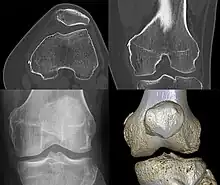

Diagnosis is typically made on radiographs demonstrating the Pellegrini-Stieda syndrome sign accompanied by pain or restriction of range-of-motion of the knee joint.[2] Pellegrini-Stieda syndrome sign is typically described by a longitudinally linear opacity, which is a process that is describes characteristic of calcification in the soft tissue located medial to the medial femoral condyle.[2] This calcification seen on imaging represents the ossification of the medial collateral ligament, which typically does not develop until approximately three weeks after the initial injury.[2]It is important to note to distinguish this radiographic finding from that of a medial femoral condyle avulsion fracture, which is an injury in which a pulling force of a tendon or ligament fractures away a piece of the bone from its attachment site.[2]

The initial injury to the knee, whether resulting from macro- or repetitive microtrauma, leads to the same result: calcific ossification of the soft tissue structures surrounding the medial femoral condyle.[2] This sprain or tear in the medial collateral ligament leads to inflammation of the area. The bodies inflammatory response lead to an immune response to try to repair leading to an abnormal healing process. The abnormalities lead to a disposition of calcium at the tear site of the medial collateral ligament which over time hardens to form a bony mass called heterotrophic ossification. As healing continues, the fibrocartilage or other disorganized tissue becomes calcified, and over weeks to months, it ossifies, forming bone-like material at the MCL attachment site.[5]

Diagnosis